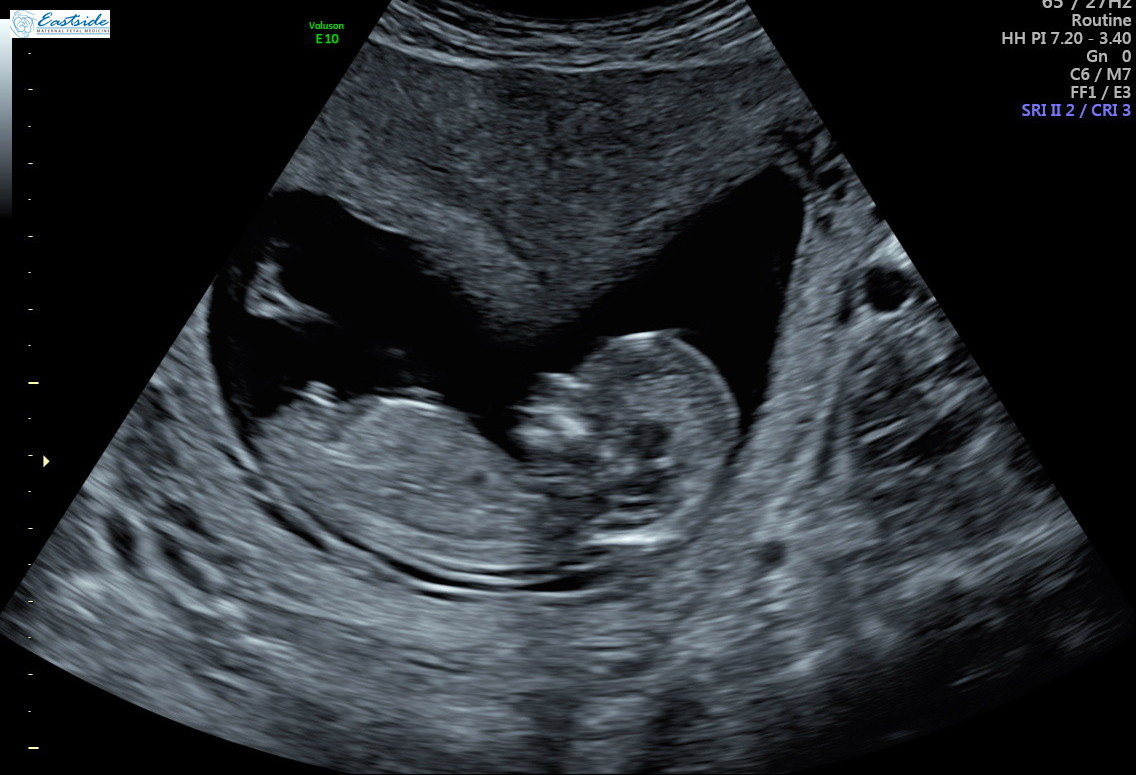

I am wondering if any experts or experienced could review the pics from my 13 week ultrasound? The tech said she was 80% sure of gender, but is it obvious to any of you? We have 3 girls so as you might guess, we are a bit anxious to find out!

Thanks! Attachment 38878Attachment 38879Attachment 38880Attachment 38881Attachment 38882Attachment 38883